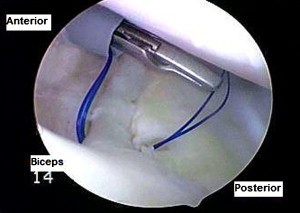

Η θεραπεία της ρήξης των μηνίσκων είναι συνήθως χειρουργική με αρθροσκόπηση. Κατά την διάρκεια του χειρουργείου ο χειρουργός αφαιρεί το σπασμένο (ρηχθέν) τμήμα του μηνίσκου (αυτή είναι η συνηθέστερη πρακτική) ή όταν οι συνθήκες το επιτρέπουν προχωρά σε συρραφή του μηνίσκου.

- Arthroscopic meniscal repair.